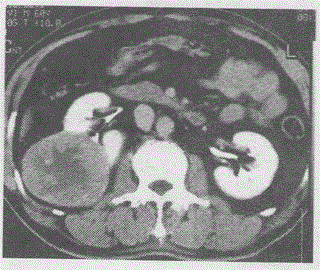

男,60岁,右侧腰部疼痛半年,CT增强如图,最可能的诊断是A.肾错构瘤B.肾癌C.肾脓肿D.肾结核E.淋巴瘤

问题 男,60岁,右侧腰部疼痛半年,CT增强如图,最可能的诊断是

选项 A.肾错构瘤 B.肾癌 C.肾脓肿 D.肾结核 E.淋巴瘤

答案 B